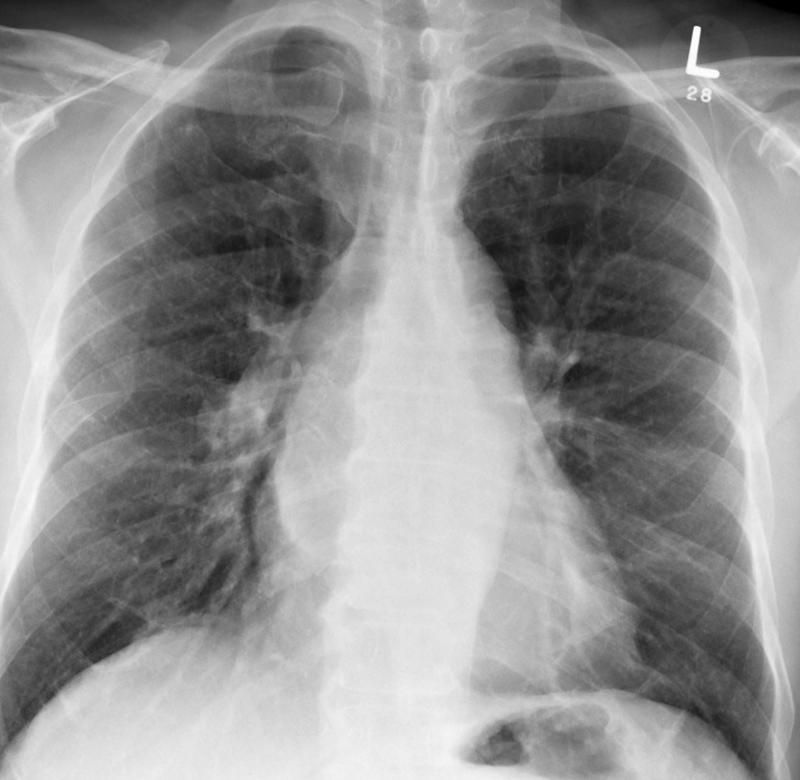

Gallery Congenital Bronch Cyst 1 PA

Bronch Cyst 1 PA